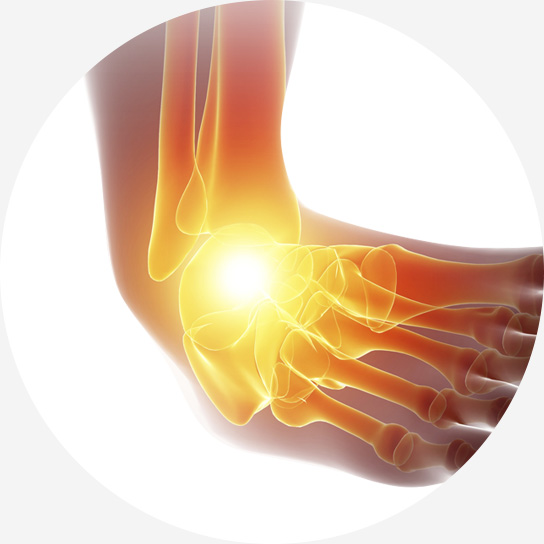

발목 인대 파열은 발목 관절을 지지하는 인대가 외부 충격이나 과도한 움직임으로 인해 늘어나거나 찢어지는 손상을 말합니다.

발목을 접질리거나 회전 손상을 입는 경우 발생할 수 있으며, 스포츠 활동 중, 낙상, 교통사고 등 다양한 원인으로 발생할 수 있습니다.

활동량이 많을수록 더 많이 발생하는 발목 염좌는 초기 치료가 중요합니다.